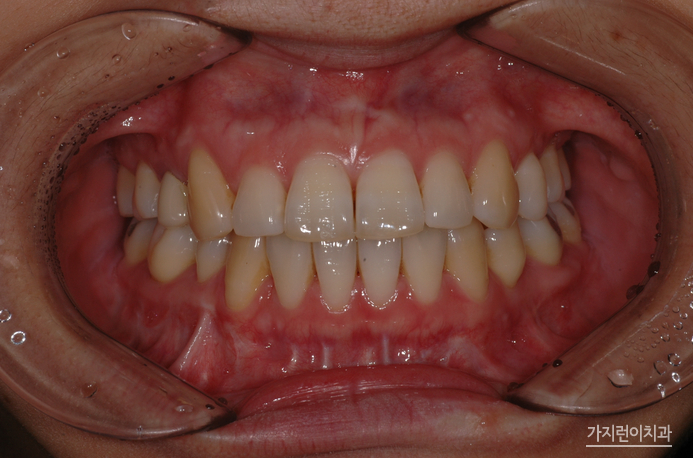

바로 이 모습입니다. 수술교정의 경우 안모변화가 큰 편인데요. 돌출되었던 입이 들어가고 턱 라인까지 정리된 모습을 얻을 수 있기 때문에 둔탁한 모습에서 날렵한 모습으로 눈에 띄게 변화한 것을 확인해볼 수 있었습니다. 여기에 가지런한 치열은 긍정적인 이미지를 불러일으키는데요. 환자의 상태에 따라서 적합한 교정방식을 선택할 수 있는 곳. 교정전문치과 서울가지런이치과 교정과 의원에서 도움 받아보는 건 어떨까요?